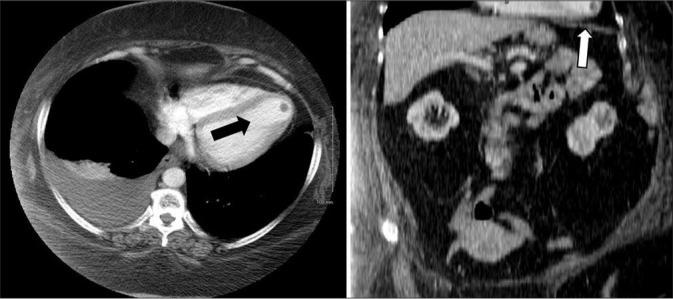

Radiologists reading multiplanar abdominal/pelvic computed tomography (CT) are vulnerable to oversight of specific anatomic areas, leading to perceptual errors (misses). The aims of this study are to identify common sites of major perceptual error at our institution and then to put these in context with earlier studies to produce a comprehensive overview.

A total of 216 missed findings were identified in 201 patients. The most common indication for the study was cancer follow-up (71%) followed by infection (11%) and abdominal pain (6%). The most common anatomic regions of error were the liver (15%), peritoneum (10%), body wall (9%), retroperitoneum (8%), and mesentery (6%). Data from other studies were reorganized into congruent categories for comparison.

This study demonstrates that the most common sites of significant missed findings on multiplanar abdominal/pelvic CT included the mesentery, peritoneum, body wall, bowel, vasculature, and the liver in the arterial phase. Data from other similar studies were reorganized into congruent categories to provide a comprehensive overview.